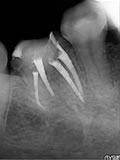

症例 24. リッジ

下顎右側第一大臼歯の遠心舌側根にリッジが起こっている症例

治療前

治療中

治療後